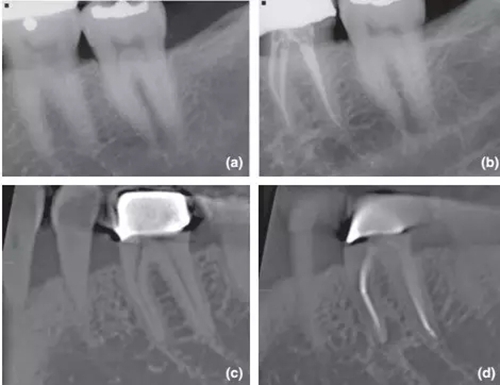

36術(shù)前X片,無根尖暗影;

1年回訪X片,根尖周無異常,診斷為成功的根管治療;

CBCT對同一個36進行術(shù)前掃描,無根尖暗影;

1年回訪使用CBCT,發(fā)現(xiàn)新出現(xiàn)的根尖暗影,診斷為和X片完全相反的根管治療失敗。

CBCT掃描不受解剖噪點影響,對根尖周組織還原度高,而且還能做出精確的線性和容積測量,這些特點都十分有利于對骨損愈合的監(jiān)控。其中最具影響力的文獻當(dāng)屬由 Patel 在2012年發(fā)表的根管治療術(shù)后1年回訪臨床實驗,是第一篇應(yīng)用CBCT進行術(shù)前及術(shù)后后掃描比較的研究。